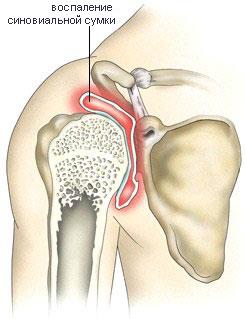

Кальцифицирующий тендобурсит (острое болезненное плечо). Возникает при реактивном воспалении сумок плечевого сустава, вызываемом кальцификатами сухожилий мышц «вращающей манжеты плеча» (рисунок). Характерна остро возникающая боль в области плечевого сустава и значительное ограничение как активных, так и пассивных движений в нем. Обычно сильные боли в области шеи, надплечья и руки.